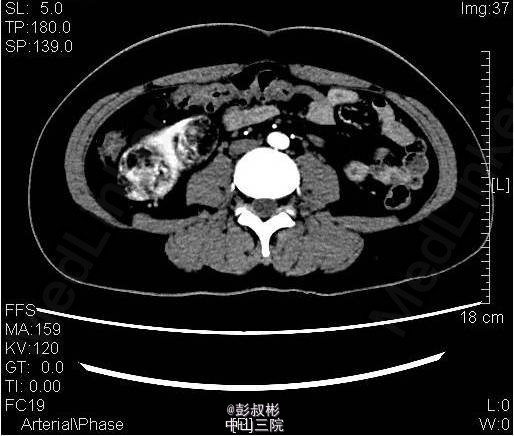

3、既往史:无特殊 4、体格检查:双肾区无红肿、隆起,左肾区叩击痛(-),右肾区叩击痛(+),左侧肋脊点、肋腰点压痛(-),右侧肋脊点、肋腰点压痛(+)。腹平软,左侧输尿管走行区压痛(-),右侧输尿管走行区压痛(-),膀胱区无膨隆,压痛阴性。 5、辅助检查:尿常规:白细胞计数27.60个/ul; 生化全套:钾3.290mmol/L;血常规:白细胞总数12.730x10E9/L,中性粒细胞绝对值9.950x10E9/L心电图、胸片正常;肿瘤抗原检查正常。ECT:右肾灌注、功能轻度降低;左肾灌注、功能基本正常。GFR:左肾为67.3ml/min,右肾为30.6ml/min。CTU:右肾体积增大,双肾可见多发大小不等结节状、团块状异常密度影,其内密度欠均匀,病灶内可见脂肪密度影,增强扫描呈不均匀强化,最大者位于右肾,约59×54mm,双肾多发错构瘤,右肾错构瘤出血。

6、入院诊断:双肾错构瘤(右肾肿物破裂出血可能) 7、处理:予心电监护、吸氧、留置尿管,引流出淡黄色尿液1600mL;急查血常规、生化未见明显异常;予抗感染、补液及营养支持治疗。拟行腹腔镜下右肾部分切除术,备右肾切除术。